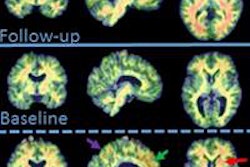

The results showed significantly higher binding levels of F-18 FDDNP in subjects with Down syndrome in all brain regions compared to healthy controls. When compared with the Alzheimer's group, the individuals with Down syndrome showed significantly higher binding levels in the parietal and frontal regions, which are associated with memory, behavior, and reasoning.

| FDDNP-PET brain scans of control subject (left) shows minimal binding compared to the other subjects. The older Down syndrome subject (center right) shows higher binding than the younger Down syndrome subject (center left). Yellow and green correspond to greater binding values, while blue corresponds to less binding. Images courtesy of UCLA. |

In the Down syndrome group, the researchers also found significant associations between increased age and greater F-18 FDDNP binding in the parietal, lateral temporal, and frontal regions.